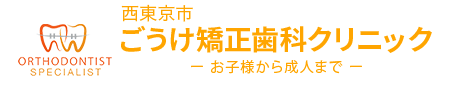

6-12歳の混合歯列期で、以下のような不正咬合の小児。

(八重歯も含む)

前歯がガタガタできちんと生えそろうか心配です・・・

すでに永久歯の生えるスペースが足りなくてガタガタしている、あるいは隣の歯のスペースがないなどの場合は、小児期の旺盛な成長力を利用して積極的にあごを拡大していきます。